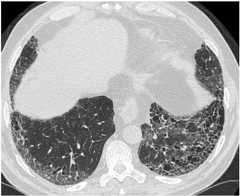

Typical HRCT pattern of UIP. The image shows subpleural and basal predominance of reticular opacities associated with traction bronchiectasis and honeycomb change (clustered cystic airspaces with well-defined thick walls and diameter of 0.3–1.0 cm)

Image: “(HRCT) pattern” by Interstitial Lung Disease Unit, Royal Brompton and Harefield NHS Foundation Trust, London, UK. License:CC BY 4.0